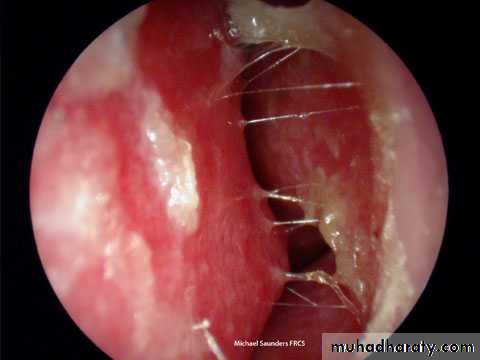

Local treatment: - Before perforation of the TM myringotomy!!

- Myringotomy {site}

Myringotomy to restart ventilation of the middle ear. Slide 18